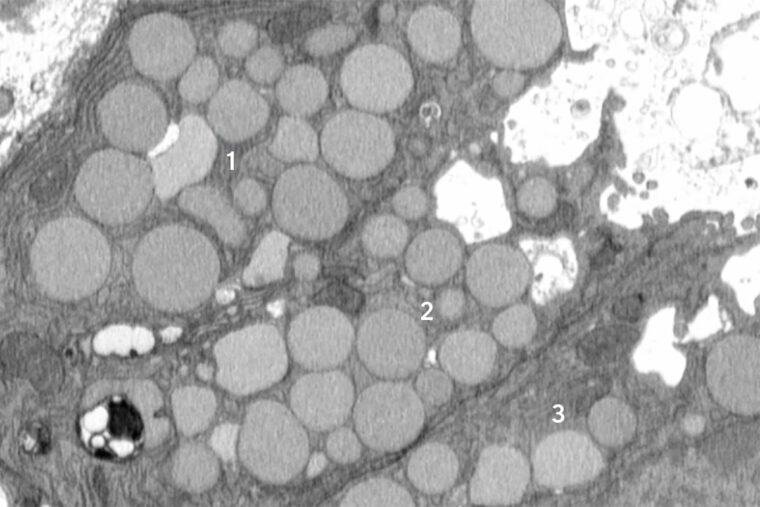

A new study from WashU Medicine identifies a previously unknown way that cells purge waste in a process that helps them revert to a stem cell-like state to promote healing after injury. Here, three mouse stomach cells (numbered) are shown jettisoning cellular debris through cavities (white) that form in their membranes. The researchers dubbed the new purging process “cathartocytosis,” combining Greek root words meaning cellular cleansing. (Image: Jeffrey Brown/WashU Medicine)